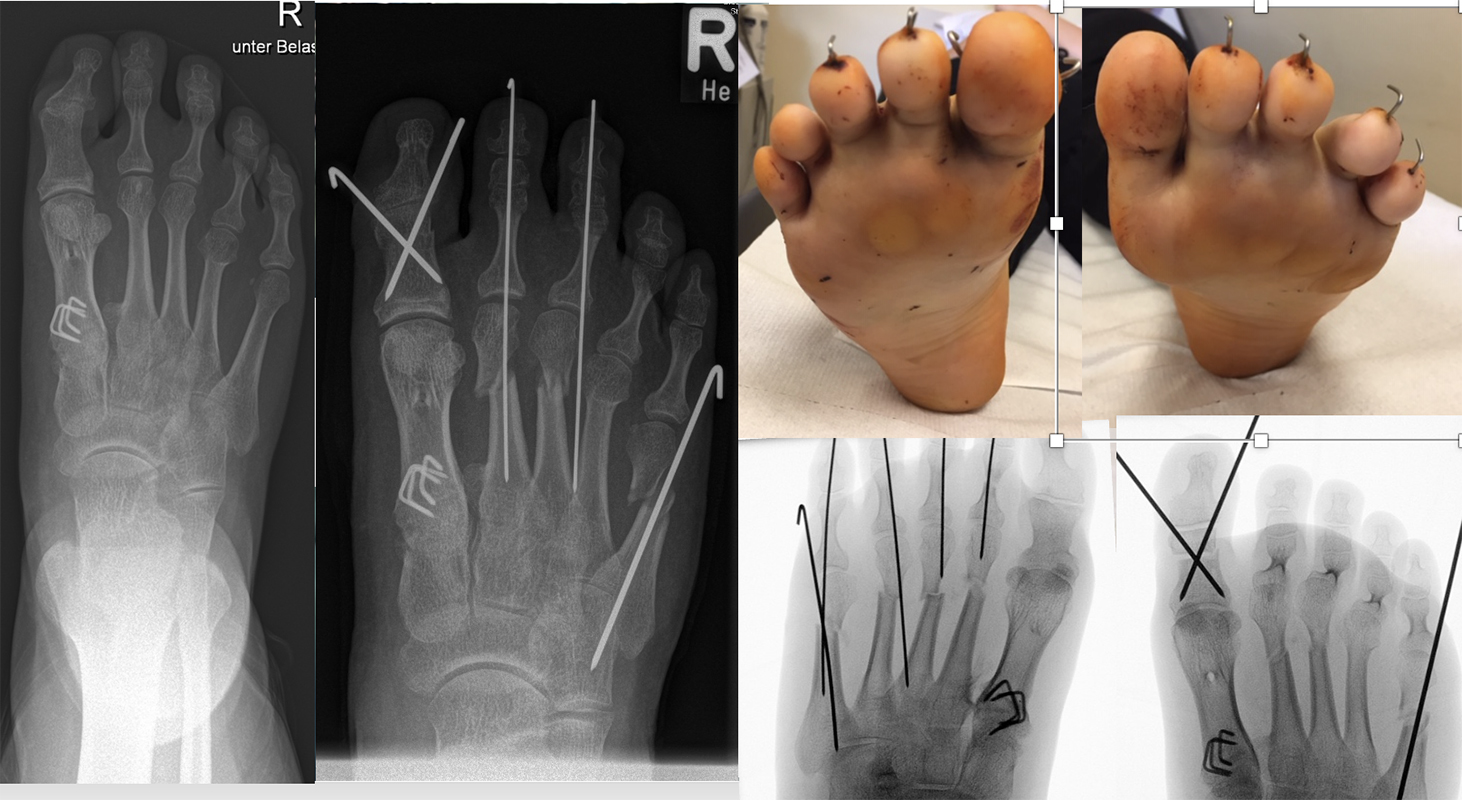

Abb. 20 a-d: Krallenzehen mit subluxierter Gelenkstellung. Präoperatives Röntgenbild d. p. (a), intraoperative Nadelmarkierung für die entsprechenden Osteotomien (b); postoperatives Röntgenbild mit einer Multilevel-Korrektur der Zehen (c) und klinischer postoperativer Verlauf (d). In der letzten Aufnahme zeigt sich gut die bereits korrigierte Zehenstellung am rechten und die noch nicht versorgten Zehen am linken Fuß.

Zum Lesen der Bildbeschreibung und zur Vollansicht bitte die Bilder anklicken. Bilder: A. Helmers.

Die Osteotomien werden ganz dem Bedarf angepasst. Es lassen sich über Verkürzung, Derotation und bei Bedarf auch Translation enorme Korrekturen erreichen. Für ein verbessertes Sehnenzuggleichgewicht kombinieren wir die Osteotomien bei Bedarf mit einem Beugesehnentransfer nach Girdlestone-Taylor (Abb. 10 und 21).

Werden komplette Osteotomien an den Zehen durchgeführt, fädeln wir die Osteotomien mit einem 1.2 oder 1.4 mm Kirschner-Draht auf, damit die einzelnen Fragmente nicht verkippen (Abb. 22).

Abb. 22 a-d: Präoperative Klauenzehen beim Jugendlichen in zwei Ansichten (a-b) und postoperative Auffädelung mit Kirschner-Drähten linker und rechter Fuß (c-d).